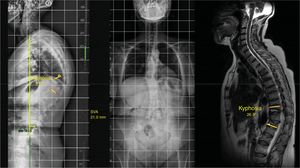

In the local deformity group (stage 1), this can be flexible (1A), if a reduction in angulation greater than 50% is observed in the decubitus position with respect to the X-ray (Fig. 2) in standing position, or rigid (1B), when no reduction is seen in the decubitus position (Fig. 3).13 Finally, this local deformity may be compensated (C) when the standing teleradiography shows the SVA to be within normal parameters, or non-compensated (NC), when the teleradiography shows an out-of-range SVA. It should be remembered that SVA varies with age, and we are not looking for as rigorous a correction in the elderly patient as in the young patient.8

Illustration of a case with stage 1 A NC, in which, without the need to perform a three-column osteotomy, very good intraoperative reduction is observed and long percutaneous T4-L2 instrumentation and vertebroplasty of L3, L4, and L5 is performed due to fractures at that level. 1 A NC: deformity secondary to angular, flexible and non-compensated osteoporotic vertebral fracture.